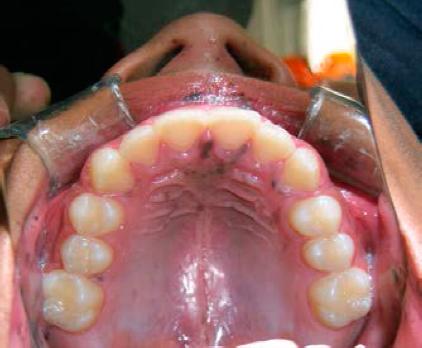

A la exploración clínica se observan múltiples máculas que confluyen entre sí en el borde bermellón del labio superior e inferior, siendo más abundantes en el labio inferior (Figura 1). Presenta también máculas generalizadas en mucosa labial y mucosa yugal (Figura 2), y sólo unas cuantas a nivel de la papila incisiva y paladar duro (Figura 3), respetando la mucosa lingual y piso de boca. El paciente presentó una mancha melánica difusa en la falange distal del dedo índice de la mano derecha (Figura 4).

Figura 2 Hipermelanosis en la mucosa yugal y comisuras de forma bilateral, en estas imágenes se puede observar que se encuentran intactas la mucosa lingual y el piso de boca.